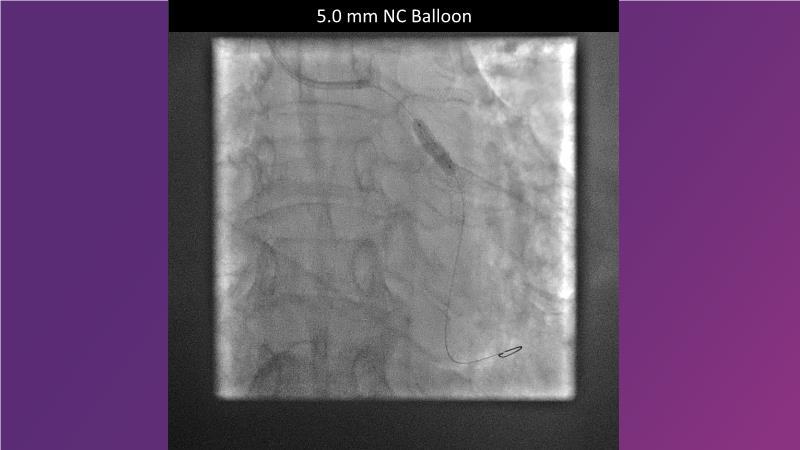

Sirolimus-coated balloon: expanding the scope of indications for complex coronary artery disease treatment

Watch this session to gain case-based insights on using DCBs in complex settings. Learn valuable tips and tricks for optimal DCB application, including the best timing and situations for their use. Discover how to effectively implement a hybrid strategy that combines DES and DCB when needed.

- To get a case based experience on how to use a DCB in complex settings